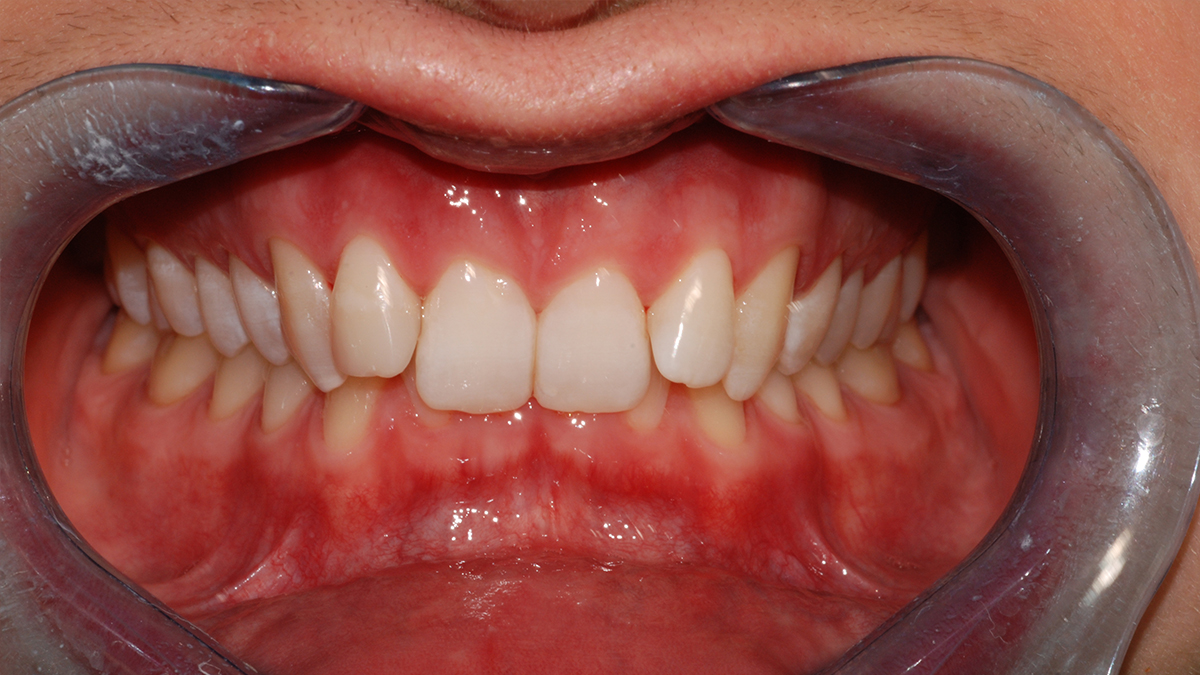

Általában ha a fognak csak egy kisebb része szuvas, a hiányzó rész kitisztítás után tömőanyaggal pótolható. A töméskészítést helyi érzéstelenítésben végezzük, egy alkalmat vesz igénybe. A tömőanyag egy speciális műanyag, kompozit, amely mind színében, mind fizikai tulajdonságaiban nagymértékben hasonlít a természetes foghoz, ezért alkalmas tartós és esztétikus tömések készítésére. Töméskészítés során a gyurmaszerű anyagot kis adagokban helyezzük az üregbe, majd az egyes rétegeket speciális lámpával világítjuk meg, melynek hatására megszilárdulnak. A tömés elkészültével az anyag kötése befejeződik, a fog terhelhető.